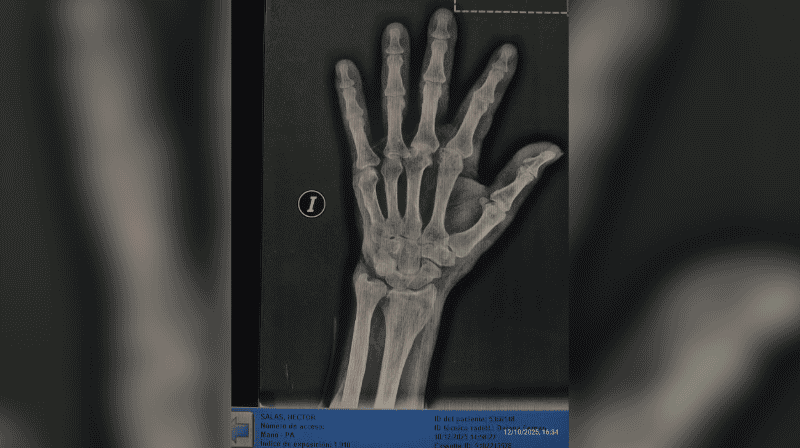

La nieta de la víctima, Karen Salas, realizó una denuncia pública a través de las redes sociales. “Él se negó a tomar una medicación y ella (la dueña del geriátrico) fue y le pegó. Según ella, dijo que le pegó porque le agarró un brote psicótico”, expresó. En su publicación, compartió imágenes del abuelo, registros de las cámaras internas del establecimiento y las radiografías realizadas después.

Luego de la agresión, Héctor fue retirado del geriátrico y trasladado a otro establecimiento. La familia indicó que, durante una revisión médica solicitada por sus nietas, se confirmaron fracturas en el dedo pulgar derecho y heridas en el rostro

La familia denunció que el hombre sufrió una fractura en el dedo pulgar.